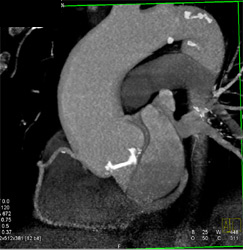

Patent LAD Stent